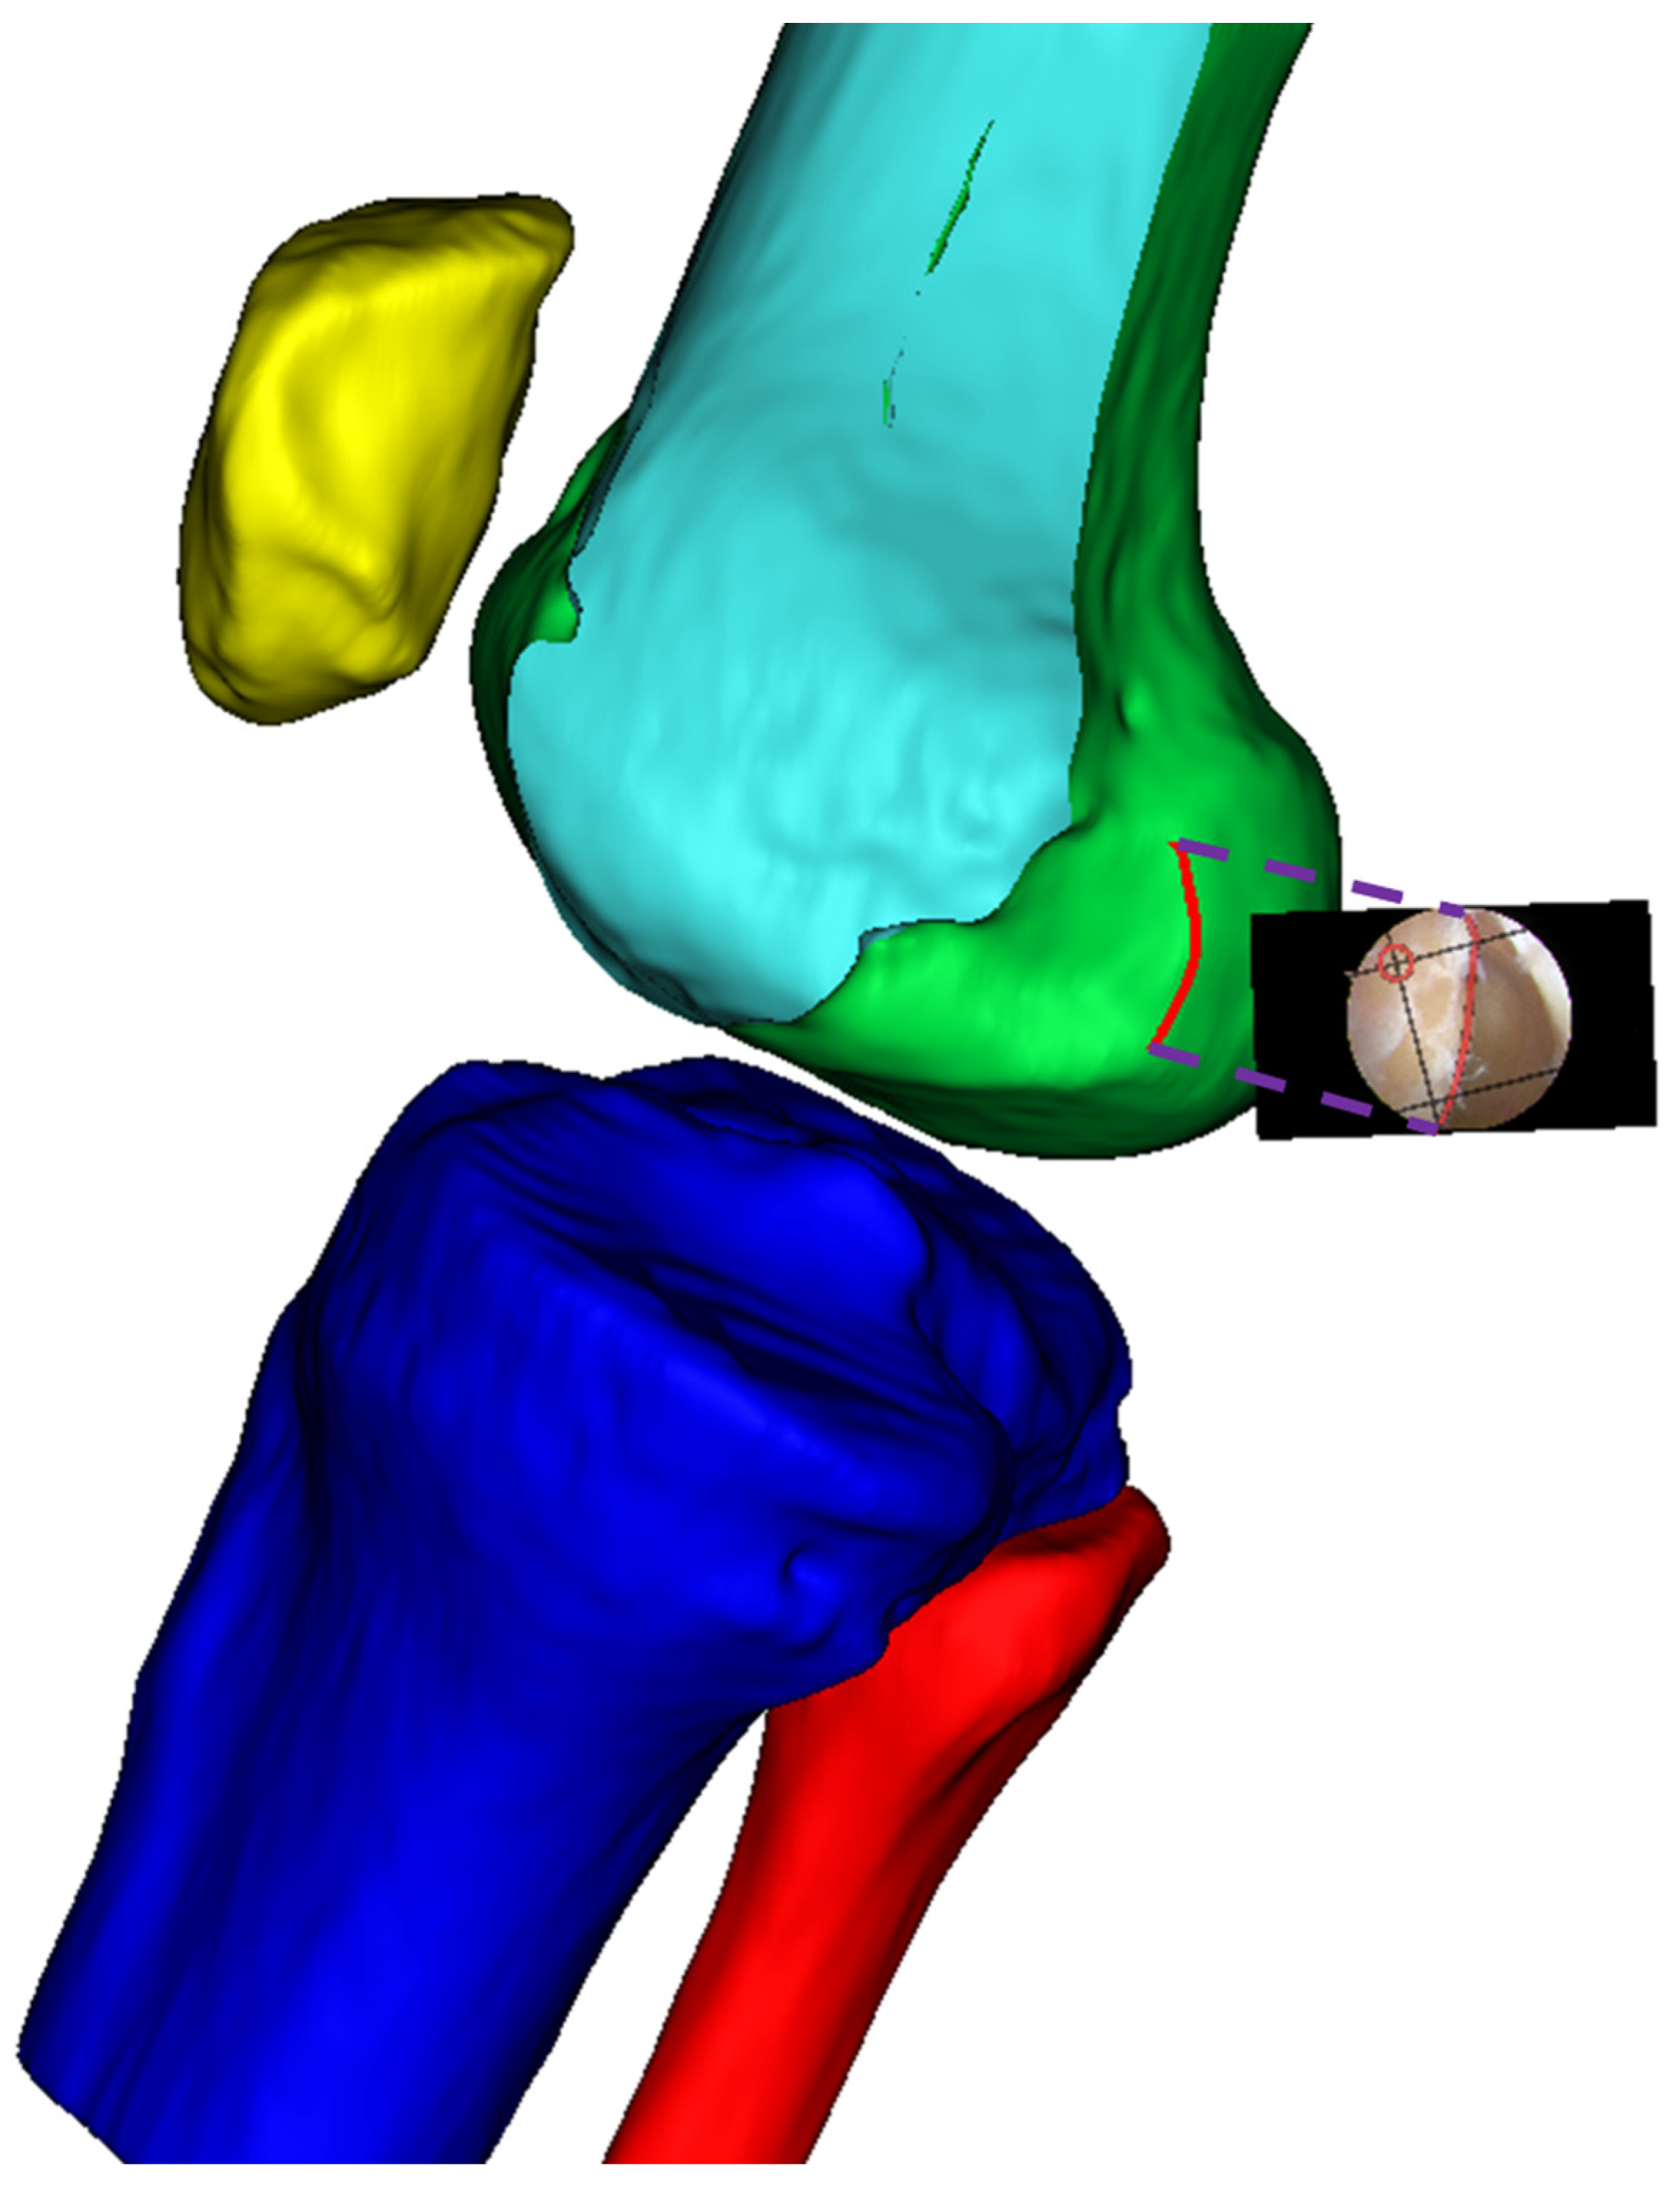

2.5. Establishment of B&H Grid on the 3D Lateral Condylar Model

2.6. Real-time B&H Grid Overlay